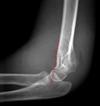

Normal XR elbow

Radial head dislocation

Classification of supracondylar fractures

Supracondylar fracture (Gartland 1 - minimally displaced)

108

Supracondylar fracture (Gartland 2 - displaced, posterior cortex intact)

Supracondylar fracture (Gartland 3 - displaced, complete)